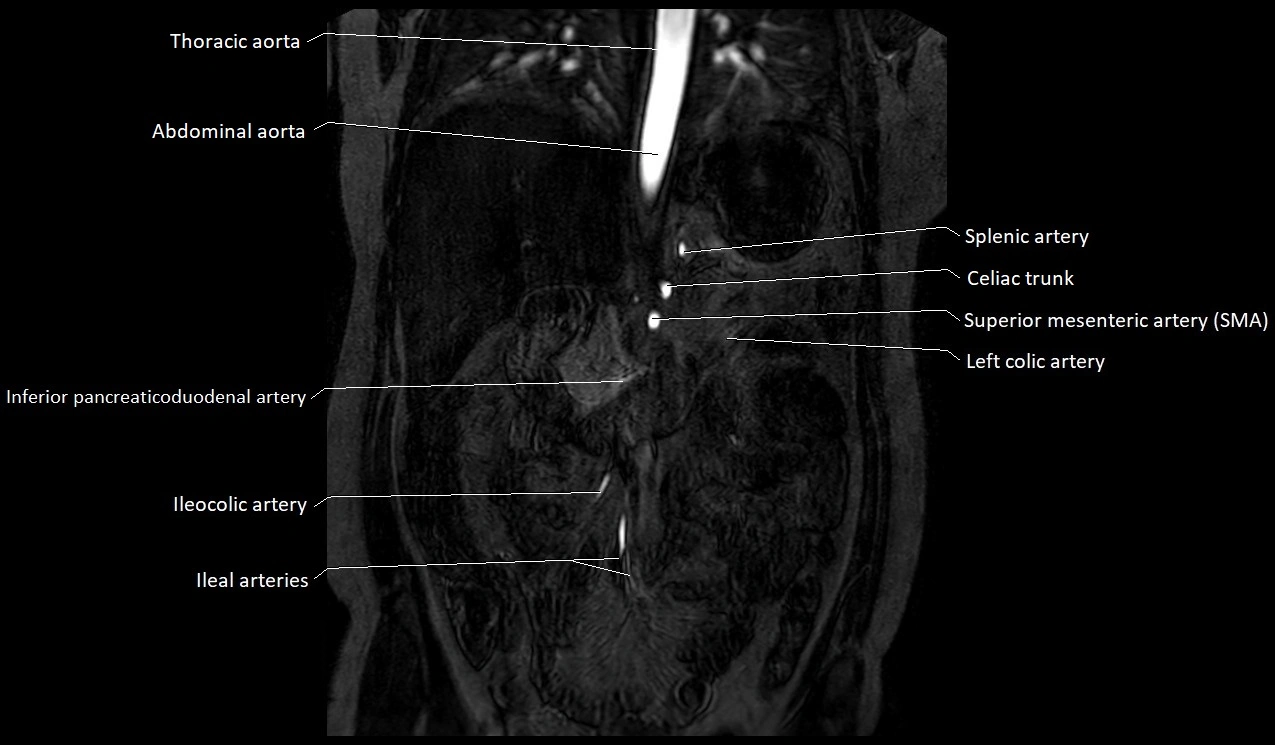

MRA Pelvis with Gadolinium:

-

Clearly delineates the origin, course, and anastomoses of the accessory obturator artery

Identifies connection with inferior epigastric artery, external iliac artery, or obturator artery

Excellent for detecting vascular variants prior to surgery

Useful in mapping pelvic vasculature in trauma, tumor embolization, or preoperative planning